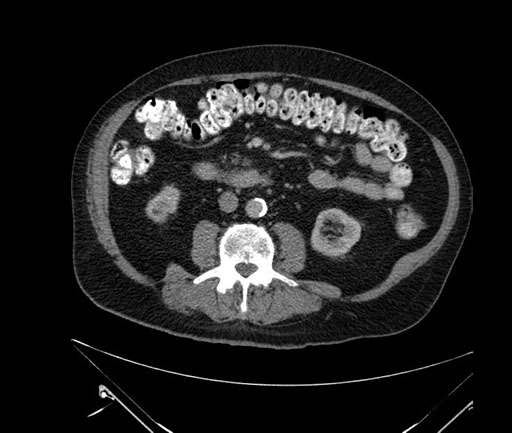

Axial - stented

Imaging analysis